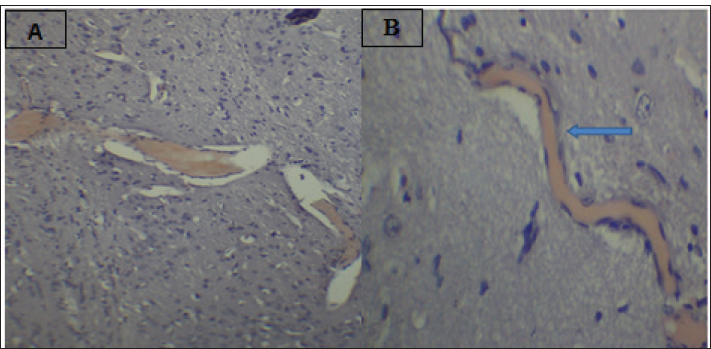

Fig. 2. Effect of gemcitabine, gemcitabine + ALC (25 mg/kg/bw), and gemcitabine + ALC (300 mg/kg/bw) on serum AChE. Histological resultsAccording to the histological investigation, the central nervous system did not contain any beta clusters. The experimental beta-amyloid turns red because it is stained using the pigment Congo red, indicating that the central nervous system is secure from beta-amyloid buildup in the absence of treatment (Fig. 3). The gemcitabine group showed an increase in beta-amyloid accumulation in the rat’s brain, which is stained in red color as shown in Figure 4. However, compared to the gemcitabine group, rats administered gemcitabine plus ALC (25 mg/kg/bw) showed a significant reduction in the buildup of beta-amyloid in the rat’s brain, as depicted in Figure 5. Furthermore, as illustrated in Figure 6, rats treated with gemcitabine + ALC (300 mg/kg/bw) exhibit a significant reduction in the buildup of beta-amyloid in their brains when compared to rats treated with gemcitabine + ALC (25 mg/kg/bw).

Fig. 4. Photomicrograph of the brain section of the gemcitabine group showing the accumulation of beta-amyloid plaques (congo red) (A 4×, B 10×).

Fig. 6. Photomicrograph of the brain section of the Gemcitabine + ALC (300 mg/kg/bw) group showed the accumulation of beta plaques (red) (4×). DiscussionGemcitabine increases the production of ROS, including superoxide radicals, which can lead to oxidative stress. The build-up of these reactive species may contribute to cellular toxicity by increasing protein oxidation, reducing enzyme activity, and compromising cell membrane integrity through lipid peroxidation. Moreover, oxidative stress may facilitate the production of secondary reactive chemicals that worsen cellular damage. Although these mechanisms offer a reasonable explanation for the toxicity caused by gemcitabine, care should be taken when interpreting them because the precise molecular pathways may differ based on the kind of tissue and the settings of the experiment. This investigation found that the fatty acid aldehydes, such as the substance and 4-hydroxynonenal, this investigation found indicating that the Gemcitabine-treated group had significantly greater variations in the bloodstream beta-amyloid levels than the remainder of the participants (Metselaar et al., 2024). The effects of gemcitabine are exclusive to the S-shaped cellular lifecycle. Significant chromosome damage causes chromosomal abnormalities. This drug thus inhibits the capacity of cells with quick division that need replication of DNA to repair individuals, potentially leading to the death of certain nerve cells (Morgillo and Marovino, 2021). Beta-amyloid may have increased in individuals who just received a combination of dying nerve cells generate a lot of amyloids in a type of beta-amyloid (Yin et al., 2021; Goel et al., 2022). ALC, and these assists in minimizing the damaging effects of oxidative stress with tissue and additionally assists in eliminating the chemical toxicology associated with gemcitabine, triggered an important decrease within the concentration of the protein beta-a within animals the fact that switched the package. Nevertheless, it has been found that a concentration of 300 mg/kg/bw was more effective in terms of effectiveness and efficiency compared with the 50 mg/kg/bw dose (Madkour et al., 2022; Wang et al., 2024). Brain beta-amyloid peptide (Abeta) may affect ache stages because ache concentrations are elevated in the vicinity of beta-amyloid plaque. Such data piqued our curiosity about the potential for the enzyme AchE as well as amyloidosis level to fluctuate within tandem, meaning that if beta-amyloid plaques rise, which is this will affect ache, which might ultimately result in cerebral suppression (Mahdi et al., 2021; Bansal et al., 2025). Histological evaluation demonstrated that the group receiving treatment had less beta-amyloid buildup and smaller beta-amyloid deposits compared to this drug category. Amyloid beta precursor amino acids are present in a variety of cellular membrane types and discharge. Amyloids quickly enter the plasma and cerebrospinal fluid. Deposits are lumps of strands and are aggregated from internalized β-amyloids, which pile on over each other as well as compress forming β-pleated or β-folded shapes (Gottwald and Röcken, 2021; Whitfield et al., 2023). Congo red pigment is frequently used to examine amyloidosis because it binds to amyloid fibrils in several components. Additionally, this appears red due to bonds (Antimonova et al., 2024). There was a notable increase in beta-amyloid levels in the Gemcitabine category resulting from the fact that Gemcitabine increases cellular stress from oxidative damage, which in turn causes an increase in beta-amyloid synthesis (Tamagno et al., 2021). Additionally, because ALC is administered, the nervous system produces less beta-amyloid due to lowering the quantity of ROS within the central nervous system, which aids their brain resulting in less beta-amyloid and, consequently, the elimination of the fluorescent red color from the tissues, as changes depicted in figures (Morid et al., 2023; Mateus et al., 2023). ConclusionAccording to the research findings, ALC reduces the negative effects of gemcitabine by primarily lowering the body’s concentrations of beta-amyloid and the buildup of the protein beta-lesions. AcknowledgmentThe authors thank the laboratory staff and colleagues for their technical support and valuable assistance throughout this study. The authors also thank the ethics committee for approving the research protocol and the institution for providing the necessary facilities. Conflict of interestThe authors declare that there is no conflict of interest. FundingNone. Authors’ contributionsMarwa Sabah Majed: Materials and Methods. Fatema Ali Al Kafhage: Results. Hiba Alameri: Discussion. Amaal Sahib Al-Zughaibi contributed to the statistical analysis of the study data. Amna Mohammed Hamza contributed to the writing and preparation of the manuscript. Roaa Noori Ali was responsible for conducting the experimental work and collecting the samples. All authors read and approved the final manuscript. Data availabilityAll data were presented in the study. ReferencesAntimonova, O.I., Polyakov, D.S., Grudinina, N.A., Masterova, K.V. and Shavlovsky, M.M. 2024. Antibodies to Congo red dye as a promising tool for detection and destruction of amyloid. Cell. Tissue. Biol. 18(6), 721–727. Ashraf, G.M. 2023. Neurochemical systems and signaling: from molecules to networks. Boca Raton, FL: CRC Press. Bansal , S., Yadav, M., Bisht, P., Bansal, D., Tushir, S. and Rathore, D. 2025. Β-Amyloid pathways in Alzheimer's disease: mechanisms and therapeutic targets. CNS Neurol. Disord-Drug. Targets. Davidová, M., Sharma, S., McMeel, D. and Loizides, F. 2022. Co-De| GT: The gamification and tokenisation of more-than-human qualities and values. Sustainability 14(7), 3787. Goel, P., Chakrabarti, S., Goel, K., Bhutani, K., Chopra, T. and Bali, S. 2022. Neuronal cell death mechanisms in Alzheimer’s disease: an insight. Front. Mol. Neurosci. 15, 937133. Gottwald, J. and Röcken, C. 2021. The amyloid proteome: a systematic review and proposal of a protein classification system. Crit. Rev. Biochem. Mol. Biol. 56(5), 526–542. Guliyeva, A., Abbasova, M. and Gadzhiev, A. 2025. Blood leukocyte formula in rats exposed to electromagnetic radiation during prenatal development. Adv. Biol. Earth. Sci. 10(3), 511–518; doi:10.62476/abes.103511 Huseynova, L. (2025). Pyruvate kinase modulation in the brain under stress factors: structural, developmental, and molecular perspectives. Adv. Biol. Earth Sci. 10(3), 488–498; doi:10.62476/abes.103488 Javan, M., Ebrahimi, M., Madatli, A., Madatli, F. and Karimova, R. (2025). Acetylation and sirtuins: molecular mechanisms driving metabolic flexibility. Adv. Biol. Earth Sci. 10(3), 547–584; doi:10.62476/abes.103547 Kıran, T.R., Otlu, O. and Karabulut, A.B. 2023. Oxidative stress and antioxidants in health and disease. J. Lab. Med. 47(1), 1–11. Lakshmanan, M. 2021. Cholinoceptor agonists and anticholinesterase agents. In Introduction to basics of pharmacology and toxicology: volume 2: essentials of systemic pharmacology: from principles to practice. Singapore: Springer, 2, pp: 3–24. Larson, A.C., Doty, K.R. and Solheim, J.C. 2024. The double life of a chemotherapy drug: immunomodulatory functions of gemcitabine in cancer. Cancer. Med. 13(10), e7287. Madkour, H., Ahmed, S. and Mohammed, W. 2022. L-carnitine ameliorates methotrexate-induced ovarian dysfunction in female rats. Records Pharm. Biomed. Sci. 6(3), 14–27. Mahdi, S.S., Albazi, W. and Hussain Al-aameli, M. 2021. The beneficial effect of glutathione in protecting the central nervous system from D-galactose-induced damage. In 1st International Ninevah Conference on Medical Sciences (INCMS 2021), Amsterdam, The Netherlands: Atlantis Press, pp 70–74. Maleki, N., Amiruddin, R., Moawad, A.W., Yordanov, N., Gkampenis, A., Fehringer, P. and Taherzadeh, M. 2025. Analysis of the MICCAI brain tumor segmentation--metastases (BraTS-METS) 2025 lighthouse challenge: brain metastasis segmentation on pre-and post-treatment MRI. arXiv preprint arXiv:2504.12527. Mateus, F.G., Moreira, S., Martins, A.D., Oliveira, P.F., Alves, M.G. and Pereira, M.D.L. 2023. L-carnitine and male fertility: is supplementation beneficial?. J. Clin. Med. 12(18), 5796. Metselaar, D.S., Meel, M.H., Goulding, J.R., Du Chatinier, A., Rigamonti, L., Waranecki, P., Geisemeyer, N., De Gooijer, M.C., Breur, M., Koster, J., Veldhuijzen Van Zanten, S.E.M., Bugiani, M., Franke, N.E., Reddy, A., Wesseling, P., Kaspers, G.J.L. and Hulleman, E. 2024. Gemcitabine therapeutically disrupts essential SIRT1-mediated p53 repression in atypical teratoid/rhabdoid tumors. Cell Rep. Med. 5(9). Morgillo, A. and Marovino, E. 2021. Chemotherapy neurotoxicity: pharmacological and toxicological aspects. Int. J. Curr. Res. 13(12), 19916–19922. Morid, O.F., Menze, E.T., Tadros, M.G. and George, M.Y. 2023. L-Carnitine modulates cognitive impairment induced by doxorubicin and cyclophosphamide in rats; insights to oxidative stress, inflammation, synaptic plasticity, liver/brain, and kidney/brain axes. J. Neuroimmune. Pharmacol. 18(3), 310–326. Tamagno, E., Guglielmotto, M., Vasciaveo, V. and Tabaton, M. 2021. Oxidative stress and -amyloid in Alzheimer’s disease which comes first: the chicken or the egg?. Antioxidants 10(9), 1479. Taub, L. 2023. Ancient Greek and Roman science: a very short introduction (Vol. 731). Oxford, UK: Oxford University Press, p: 731. Tauffenberger, A. and Magistretti, P.J. 2021. Reactive oxygen species: beyond their reactive behavior. Neurochem. Res. 46(1), 77–87. Virmani, M.A. and Cirulli, M. 2022. The role of L-carnitine in mitochondria, prevention of metabolic inflexibility and disease initiation. Int. J. Mol. Sci. 23(5), 2717. Wang, W., Pan, D., Liu, Q., Chen, X. and Wang, S. 2024. L-carnitine in the treatment of psychiatric and neurological manifestations: a systematic review. Nutrition 16(8), 1232. Whitfield, C.J., Cavaliere, E., Baulch, H.M., Clark, R.G., Spence, C., Shook, K.R. and Wolfe, J.D. 2024. An integrated assessment of impacts to ecosystem services associated with prairie pothole wetland drainage quantifying wide-ranging losses. Facets 9, 1–15. Yi, E., Chamorro González, R., Henssen, A.G. and Verhaak, R.G.W. 2022. Extrachromosomal DNA amplifications in cancer. Nat. Rev. Genet. 23(12), 760–771. Yin, X., Qiu, Y., Zhao, C., Zhou, Z., Bao, J. and Qian, W. 2021. The role of amyloid-beta and tau in the early pathogenesis of Alzheimer’s disease. Med. Sci. Monitor. Int. Med. J. Exp. Clin. Res. 27, e933084-1. Zulfugarova, P.A., Humbatov, S.I. and Mekhtiev, A.A. 2025. Molecular mechanisms of adaptation to desynchronization stress. Adv. Biol. Earth Sci. 10(3). | ||